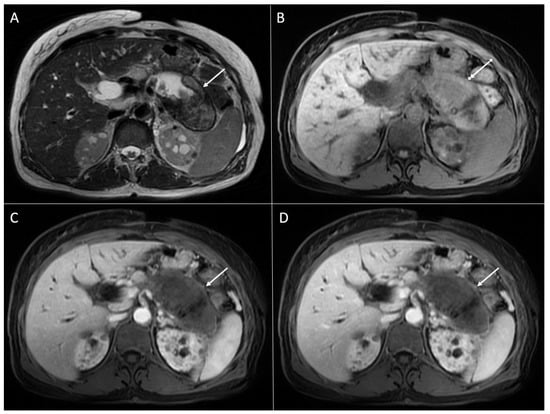

2. Typical Imaging Presentation of Solid Pseudopapillary Neoplasms